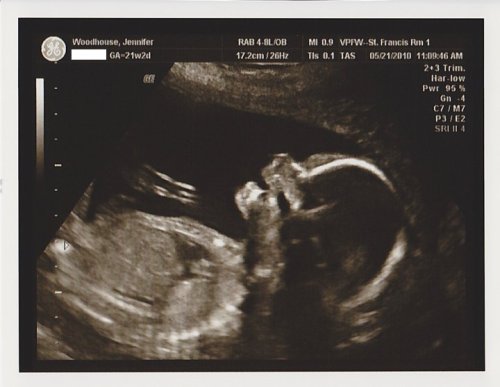

Judging from our 21 week ultrasound, it looks like our little Eggroll has her sense of humor safely intact. Doesn’t she look like she’s laughing? Bring on Daddy’s corny jokes… we’re ready!